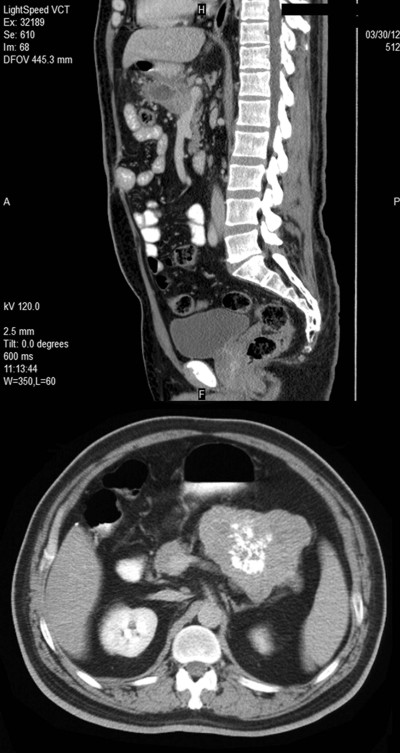

We report the case of a forty-eight year-old man with a giant mass in the pancreas, incidentally discovered during an abdominal ultrasonography on January 2012 in another hospital. The mass was later investigated by multidetector computed tomography which showed a 11 cm lobulated solid mass in the body and tail of pancreas including intensive calcifications. The mass was shown to be infiltrating splenic artery and vein. Considering the lobulated appearance of the lesion, radiologists suggested the possibility of a gastrointestinal stromal tumor or pancreas cancer (Figure 1). Magnetic resonance imaging showed an 11 cm cystic mass with a heterogeneous intensity pattern in the body and tail of the pancreas (Figure 2). The mass seemed to be attached to proximal segment of jejunum. The cystic-necrotic lobulated lesion with the heterogeneous pattern of the mass confirmed the CT diagnosis. Routine laboratory tests including carcinoembryonic antigen (CEA) and CA 19-9 were within the normal range. On January 2012 laparotomy was done and a neoplastic mass involving the body and tail of the pancreas, with encasement of the posterior part of stomach was found. Splenic hilum and mesentery of transverse colon were infiltrated by the tumor. There were no metastatic lesions in the liver or distant organs. The posterior part of the stomach was liberated by blunt dissection. En-block resection of distal pancreas, spleen and segmentally of transverse colon was performed as the mass was thought to be locally advanced pancreas tumor. The end sides of transverse colon were anastomized to each other. The postoperative course was uneventful and the patient was discharged from the hospital 4 days after surgery.

Figure 1. CT of the abdomen showing a large, lobulated solid-cystic mass in the body and tail of pancreas including intensive calcifications. |